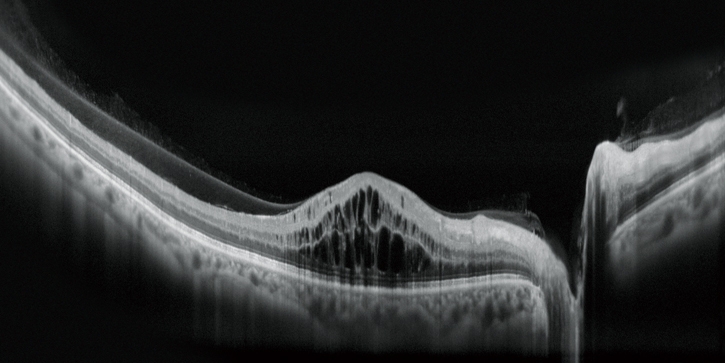

高清廣域OCT*

Mirante的掃描區域可達16.5 x 12毫米,單次拍攝就可實現包括黃斑和視盤的廣域診斷。超精細模式和高清自動追蹤功能可提供從玻璃體到脈絡膜的高質量圖像來觀察細微的病理改變。

Fly同步瀏覽功能

Fly同步瀏覽功能可滾動查看同一區域不同模式的影像,極大地提高了多模態成像的實用性。